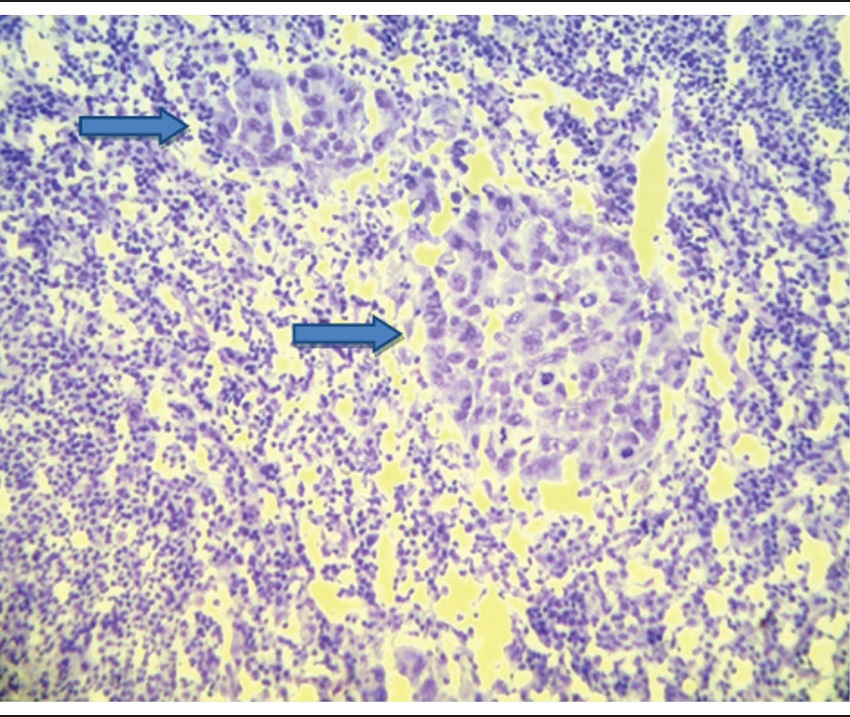

The CP technique employed was by imprint (transfer) or by scraping the cut surface of the lymph node on its longest axis. The slides were fixed in 70% alcohol and stained by toluidine blue (Figure 1).

CP (Figure 1) was positive in 15 lymph nodes and negative in 168. There was one false-positive case (6.67%) and six false-negative cases (3.57%). The sensitivity of the test was 70% and the specificity was 99.38%. PPV and NPV were, respectively, 93.33% and 96.42%. The accuracy found in this test was 96.17%.